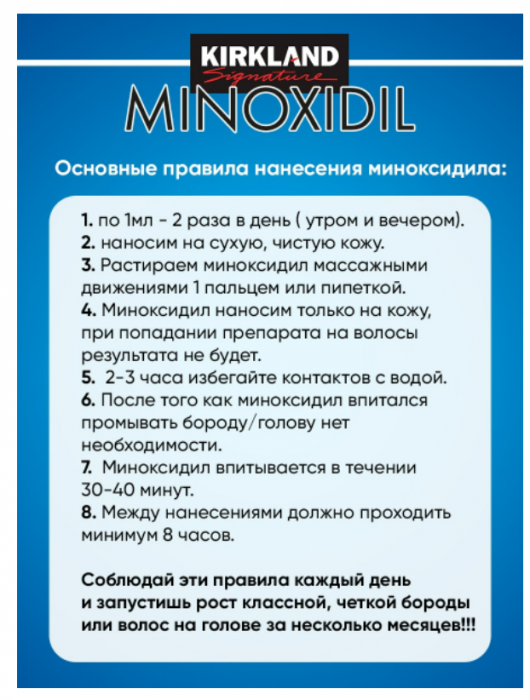

1 590 ₽/шт.0 ₽/шт.

АртикулAS-5278508